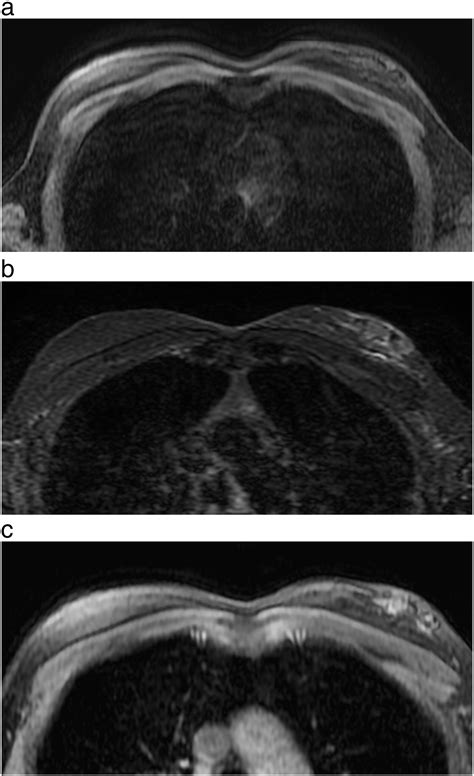

• Imaging Tests: Imaging tests such as mammography, ultrasound, or MRI may be used to visualize the affected tissue and rule out other conditions.